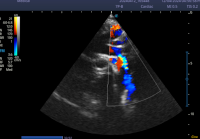

Correlation Between CHA₂DS₂-VASc Scores and Left Atrial Measurements: A Single-Center Retrospective Study

Haluk Furkan SAHAN , Sadik Acikel , Nurcan Ertan , Engin Algul , Nail Burak Ozbeyaz , Hamza Sunman , Tolga Cimen , Murat Tulmac

Abstract 374 | PDF Downloads 237 EPUB Downloads 177 | DOI https://doi.org/10.71480/nmj.v66i2.551

Page 440-448